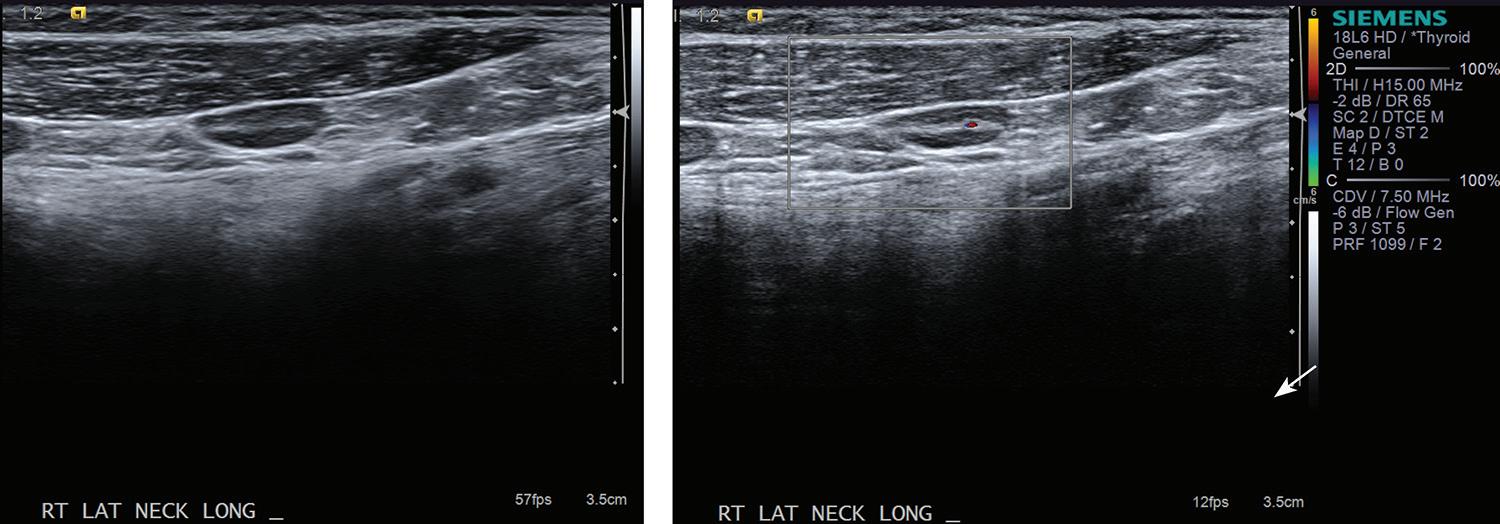

Robert J. DeFatta, MD, PhD

31 Elastography as a potential modality for screening cervical lymph nodes in patients with papillary thyroid cancer: A review of literature

Robert Saadi, MD; Salvatore LaRusso, MEd; Kanupriya Vijay, MD; David Goldenberg, MD